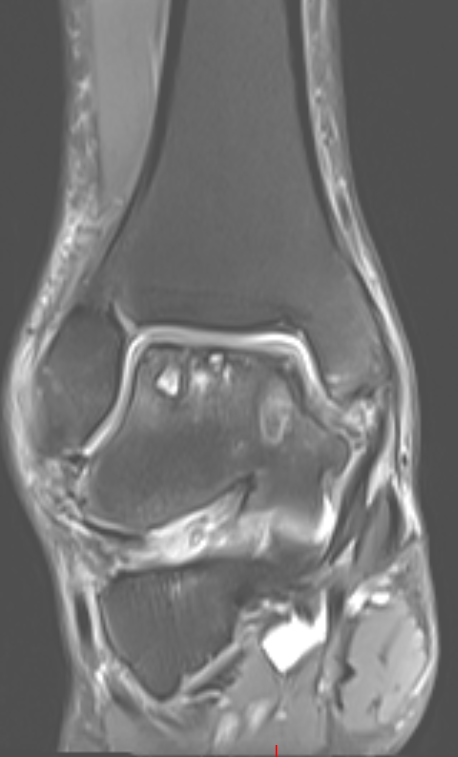

第二位是54岁的大哥,“脚脖子”痛了3年,检查发现只有部分距骨出了问题。

术前磁共振

术前CT

针对这种局部病变,团队用了3D打印部分距骨置换术。

这种手术不用大动,只换病变的那部分距骨,尽量保住健康的关节组织,创伤小,术后恢复起来也能快一点。